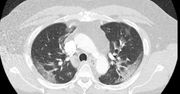

Prof. Andrzej Matyja, prezes Naczelnej Izby Lekarskiej, poinformował, że w Polsce pojawił się nowy objaw koronawirusa, który wcześniej nie występował, a teraz skarży się na niego większość pacjentów. Przekazał także, że hospitalizacji z powodu COVID-19 wymaga coraz więcej młodych ludzi.